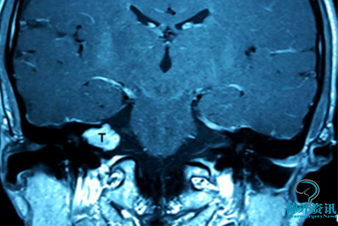

患者男性,34岁,诉右耳持续性耳鸣伴听力下降2月,头颅MRI示右侧内听道及桥小脑角区占位,初步诊断为听神经瘤。肿瘤直径约13mm×7mm,因术前纯音测听显示右耳已无实用听力,因此决定采用经迷路径路。

术前增强MRI示右侧内听道与桥小脑角区占位,薄层颞骨CT检查示右侧内听道扩大。